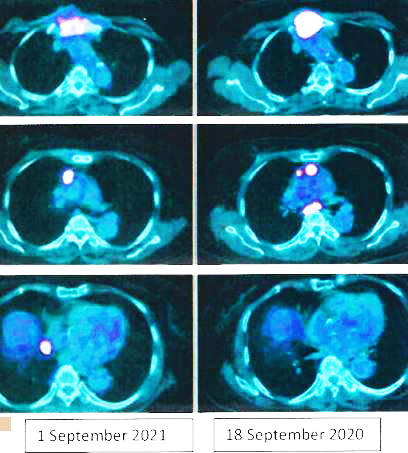

My bone has been a weak part of the body with sports injuries. I played hockey during my secondary school years and had falls. Finally I had a car accident resulting in multiple fractures and the tibia was nearly broken. Although the oncologist said it’s stabilized in June without further metastasis the CT scan showed T4, T9, T12 were fractured and these caused great pain. I felt much better now with the help of pain and bone teas.